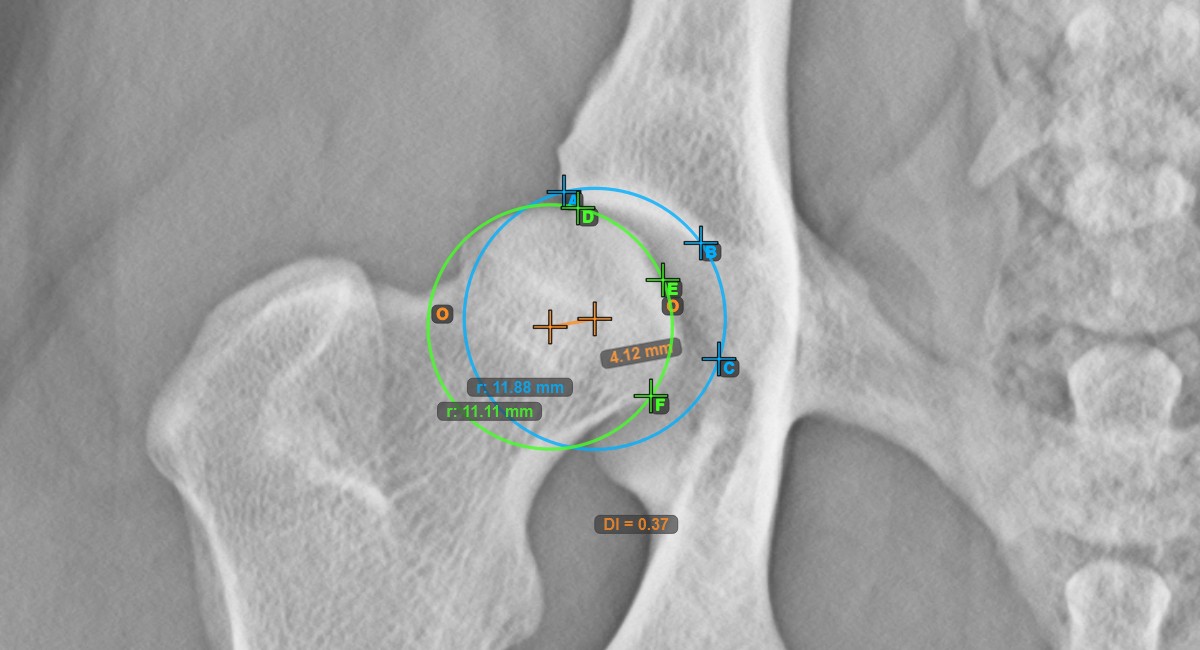

Mark the three points on the articular surface of the ipsilateral Caput Femoris to calculate the distraction index.

Mark the three points along the articular surface of the ipsilateral Caput Femoris. Regardless of the order, make sure to mark the most cranial point, the most caudal point and the midpoint of the femoral head. A circle will be automatically constructed based on the three placed points.

The Hip Distraction Index will be automatically calculated as the ratio between the distance between the two origos and the radius of the circle along the articular surface of the Caput Femoris.

The image below represents a typical placement of the three points on the articular surface of the Caput Femoris.

Modify the position of each point marked on the Acetabularis or the Caput Femoris to automatically recalculate the Hip Distraction Index.